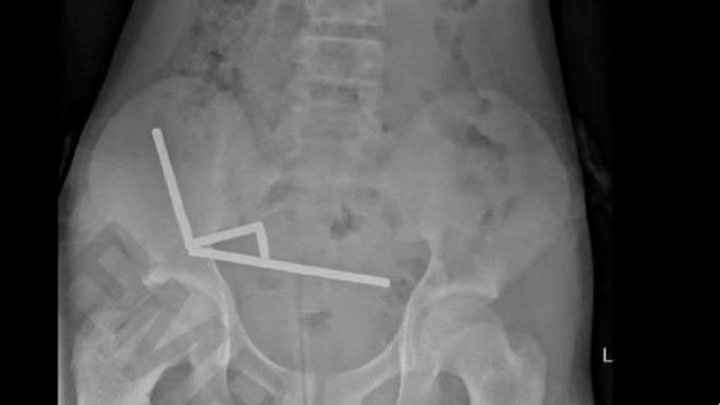

Una radiografía reveló “cadenas” de imanes en distintas secciones del intestino: cuatro agrupaciones metálicas que se habían unido a través del tejido y estaban dañando seriamente órganos vitales.